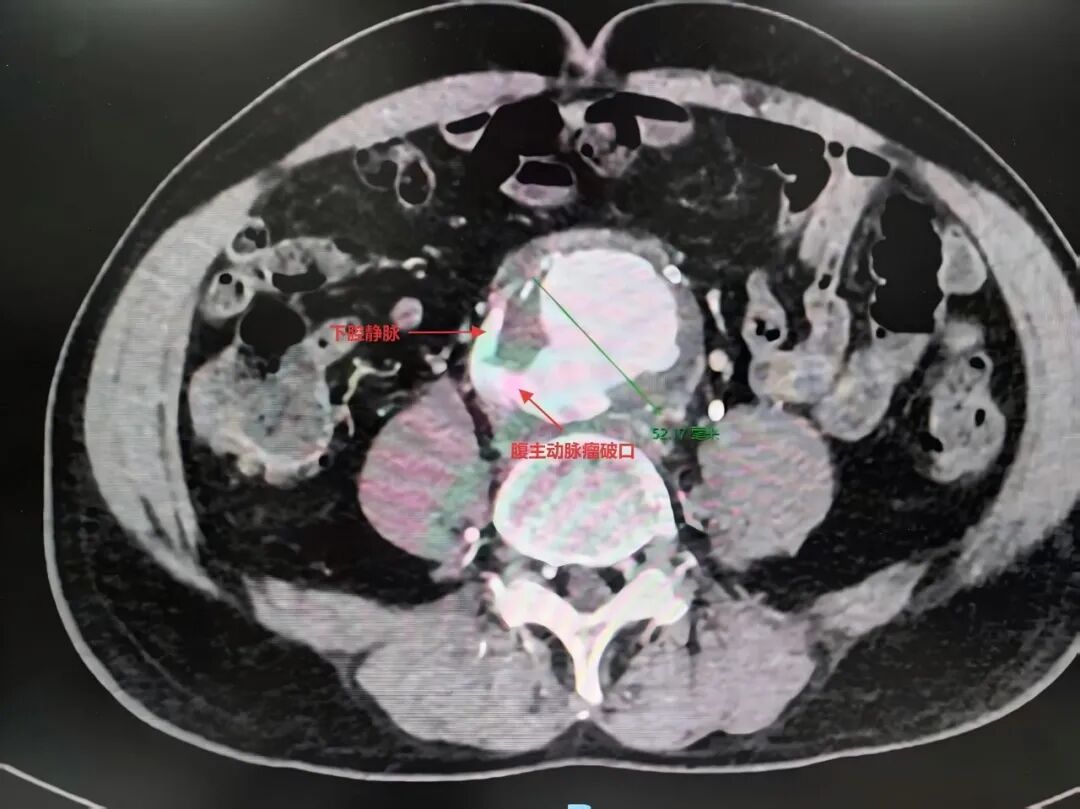

腹部CT血管成像提示:腹主动脉瘤破裂,破口与下腔静脉相通,形成腹主动脉-下腔静脉瘘;下腔静脉下段因瘤体压迫严重狭窄;左髂静脉血栓形成。

瘤体切除与瘘口修补:切开瘤体后,明确可见其向后壁破裂,并与下腔静脉形成巨大瘘口。心血管外科团队果断切除了感染的腹主动脉瘤壁,随后以5-0 Prolene血管缝线精准修补了下腔静脉破口,彻底消除了动静脉分流这一致命隐患。